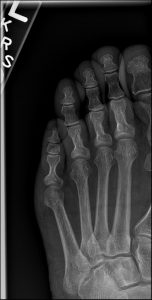

For a fracture, imaging is not just helpful; it is absolutely necessary. For a suspected toe fracture, plain film X-ray is the essential diagnostic tool.

We must obtain high-quality X-rays of the foot and toe. A minimum of two views—like the anteroposterior (AP) and oblique view—is required to visualize the fracture in 3D.

Radiographic features seen in this type of fracture would include:

Fracture Line: A visible line of discontinuity in the bone’s structure. For a simple Bedroom Fracture, this might be a fine, hairline crack that is subtle.

Location: The break is clearly seen in the proximal phalanx of the fourth toe.

Fracture Type: The pattern is important—is it transverse, oblique, or perhaps comminuted?

Displacement: Most critically, the image shows whether the bone fragments are in good alignment (non-displaced) or if they have significantly shifted (displaced or angulated). A displaced fracture may require manual reduction.

X-ray: Essential and sufficient. It clearly visualizes the bone break and is the foundation for diagnosis and management.